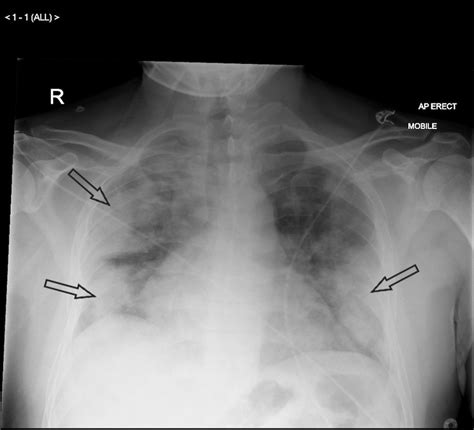

• Bronchopneumonia (Patchy Opacities): Common in hospital-acquired infections or atypical pathogens, this pattern presents as scattered, poorly defined opacities throughout one or both lungs, rather than being confined to a single lobe.

Bronchopneumonia Bacterial, Hospital-acquired Patchy, multifocal consolidations, often bilateral.